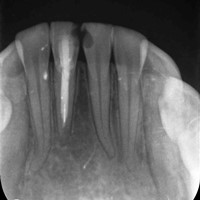

Wskazania do wykonania resekcji zębów 21, 22. Prawie niewidoczna blizna pooperacyjna.